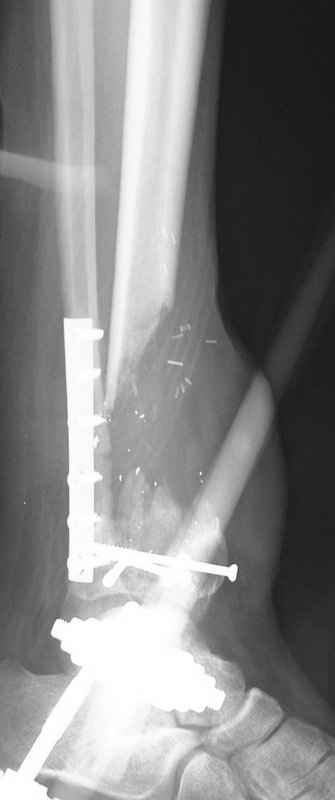

1 - рентгенограмма (прошу прощения за качество) при поступлении;

2 - внешний вид голени;

Произведено ПХО, acute shortening (5 см), фиксация стержневым аппаратом Hoffman.

3,4 - через 4 недели наложен спице-стержневой аппарат, произведена остеотомия большеберцовой кости в верхней трети, раны зажили, проводилась дистракция в аппарате.